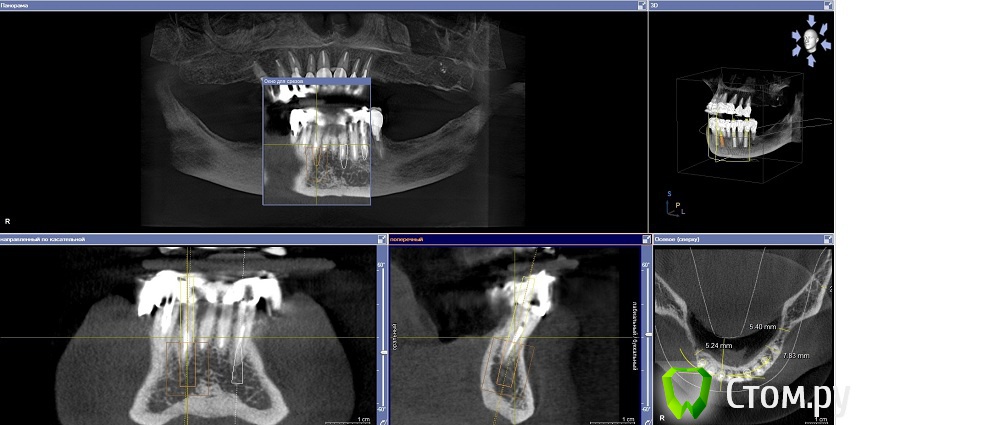

Dr.Sham Опубликовано 14 октября, 2014 Поделиться Опубликовано 14 октября, 2014 (изменено) Планируется удаление всех зубов на НЧ. Пациентка хочет несъемную конструкцию.Вот нарезка.Планируется имплантация Ankylos в позициях 46, 44, 42, 32, 34, 36.В боковых отделах дефицит всего.Думаю удалить зубы через один, чтобы на них временная конструкция держалась, а в промежутках имплантаты.В переднем отделе узко, либо узкие ФДМки, либо заглушка и в овоид край времянок или закрыть свободным трансплантатом.Что думаете?В боковых отделах вопрос...короткие имплантаты и НКР? От сложной костной пластики пациентка отказывается категирочески. Сверху пациентка так же хочет несъем. Поэтому все на 4-х, наверное, не самамя удачная конструкция здесь. Зубы сохранить никак, преп под десной местами по 3 мм. ну и дентин весь мягкий. Изменено 14 октября, 2014 пользователем Dr.Sham Ссылка на комментарий

MayTaraki Опубликовано 14 октября, 2014 Поделиться Опубликовано 14 октября, 2014 Всё на 6 В боковых отделах НКР там 1- 2 мм не хватает по сути Ссылка на комментарий

Mane Опубликовано 15 октября, 2014 Поделиться Опубликовано 15 октября, 2014 Добрый вечер. Можно вариант Дмитрия. А можно и : Ваксап 12 зубов на н/чОртопедический шаблон на н/ч Операция: удаляете все сразу 4 имплантата 34-32-42-44 - по длиннее - чтоб торк точно был. В боковых отделах поставьте коротыши и НКР по толщине сделайте. перед установкой имплантатов, как сказал Дмитрий, выровняйте гребень во фронтальном отделе - чтоб с боковыми отделами не было большого перепада - коромысла. Срузу после операции нагружайте эти 4 имплантата несъемной конструкцией лабораторного изготовления. Если требуется, можно и по десне поработать в первую операцию. Удачи. На анкилозе есть же коротыши! 4 Ссылка на комментарий

Дмитрий Никитюк Опубликовано 15 октября, 2014 Поделиться Опубликовано 15 октября, 2014 Мысли в слух: планировать нужно, исходя из будущего протезирования обеих челюстей. Я посмотрел на верх и, учитывая возраст пациентки (69 лет), понимаю, что вряд ли там будет синус и 8 имплантатов. Там скорее всего будет или съёмный протез, или максимум 6 имплантатов (пусть топикстартер поправит, если не так). Поэтому на н.ч. вполне достаточно 4 импланта. Два из них под углом 30 °, с выходом платформ на область вторых премоляров, два других между ними (нет разницы в каких позициях). Почему не больше имплантатов? А зачем больше? Лучше эти деньги потратить на довольно дорогостоящую, но очень продуманную систему SmartFix. Каждый дополнительный имплантат будет лишь удорожать конструкцию и усложнять технологический этап. А 12 зубов на н/ч вполне достаточно. Ну и не будем забывать, что нижняя челюсть во время функции меняет геометрию, что вынуждает нас при дистально расположенных опорах делить конструкцию на части.Также от будущей судьбы верхнего зубного ряда зависит и материал постоянной конструкции на н/ч, но это будет потом. 1 Ссылка на комментарий